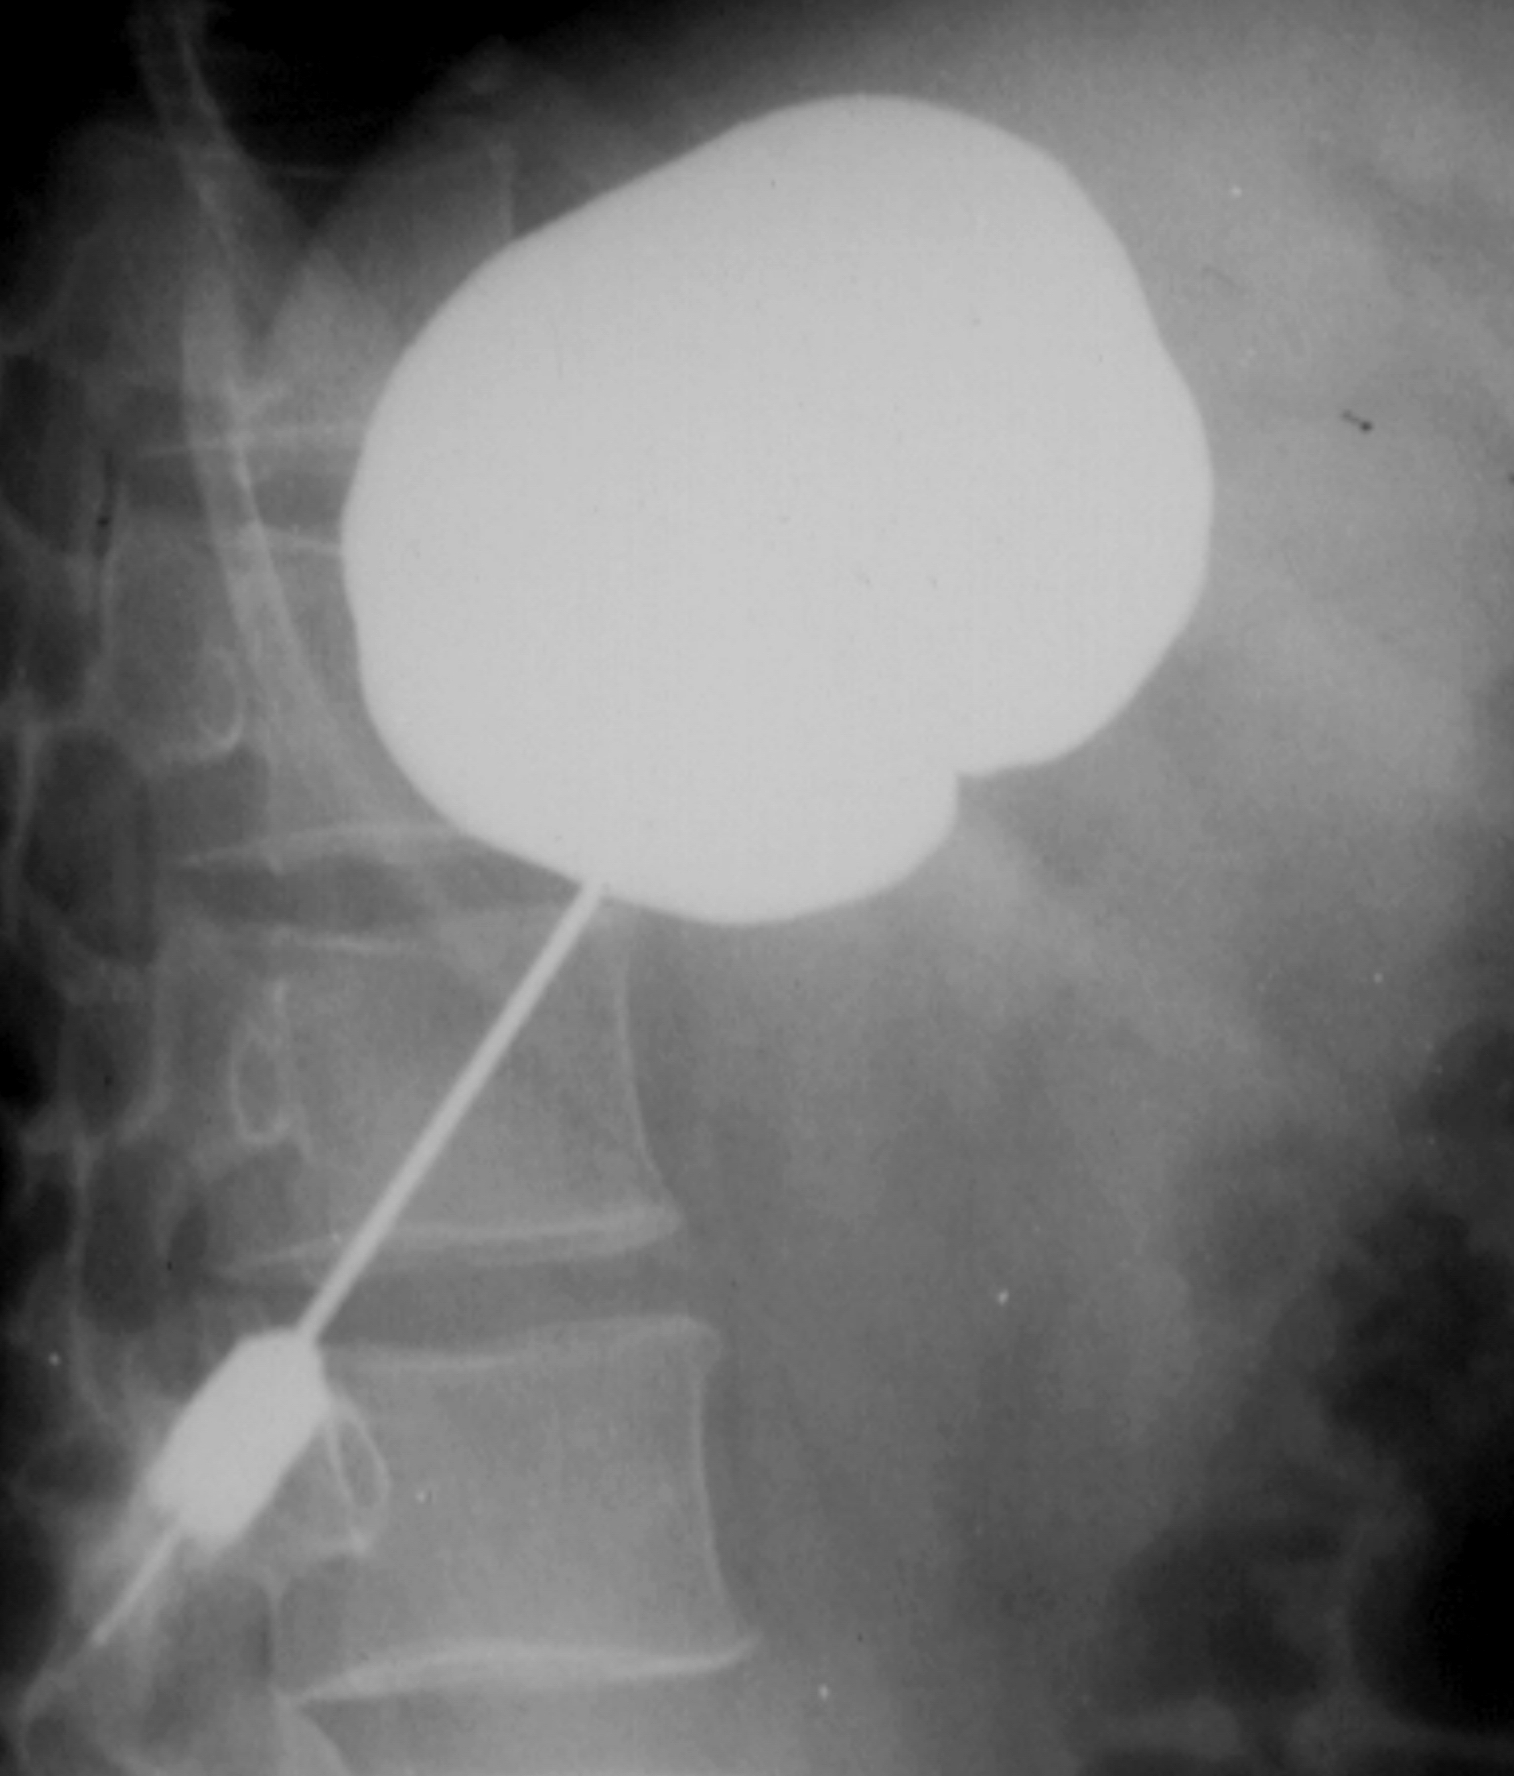

The most commonly performed intervention is US guided percutaneous nephrostomy. In special cases (obesity, visualization difficulties with US) CT guidance can also be chosen to create percutaneous nephrostomy. (Figure 30.)

Image

Figure 30. – Percutaneous nephrostomy contrast X-ray examination (CT guided catheter insertion)

In case the insertion of the catheter is not possible through the bladder in a retrograde manner, then the benign or malignant stenosis can be both overcome by inserting a hydrophilic – so called double J catheter – percutaneously.